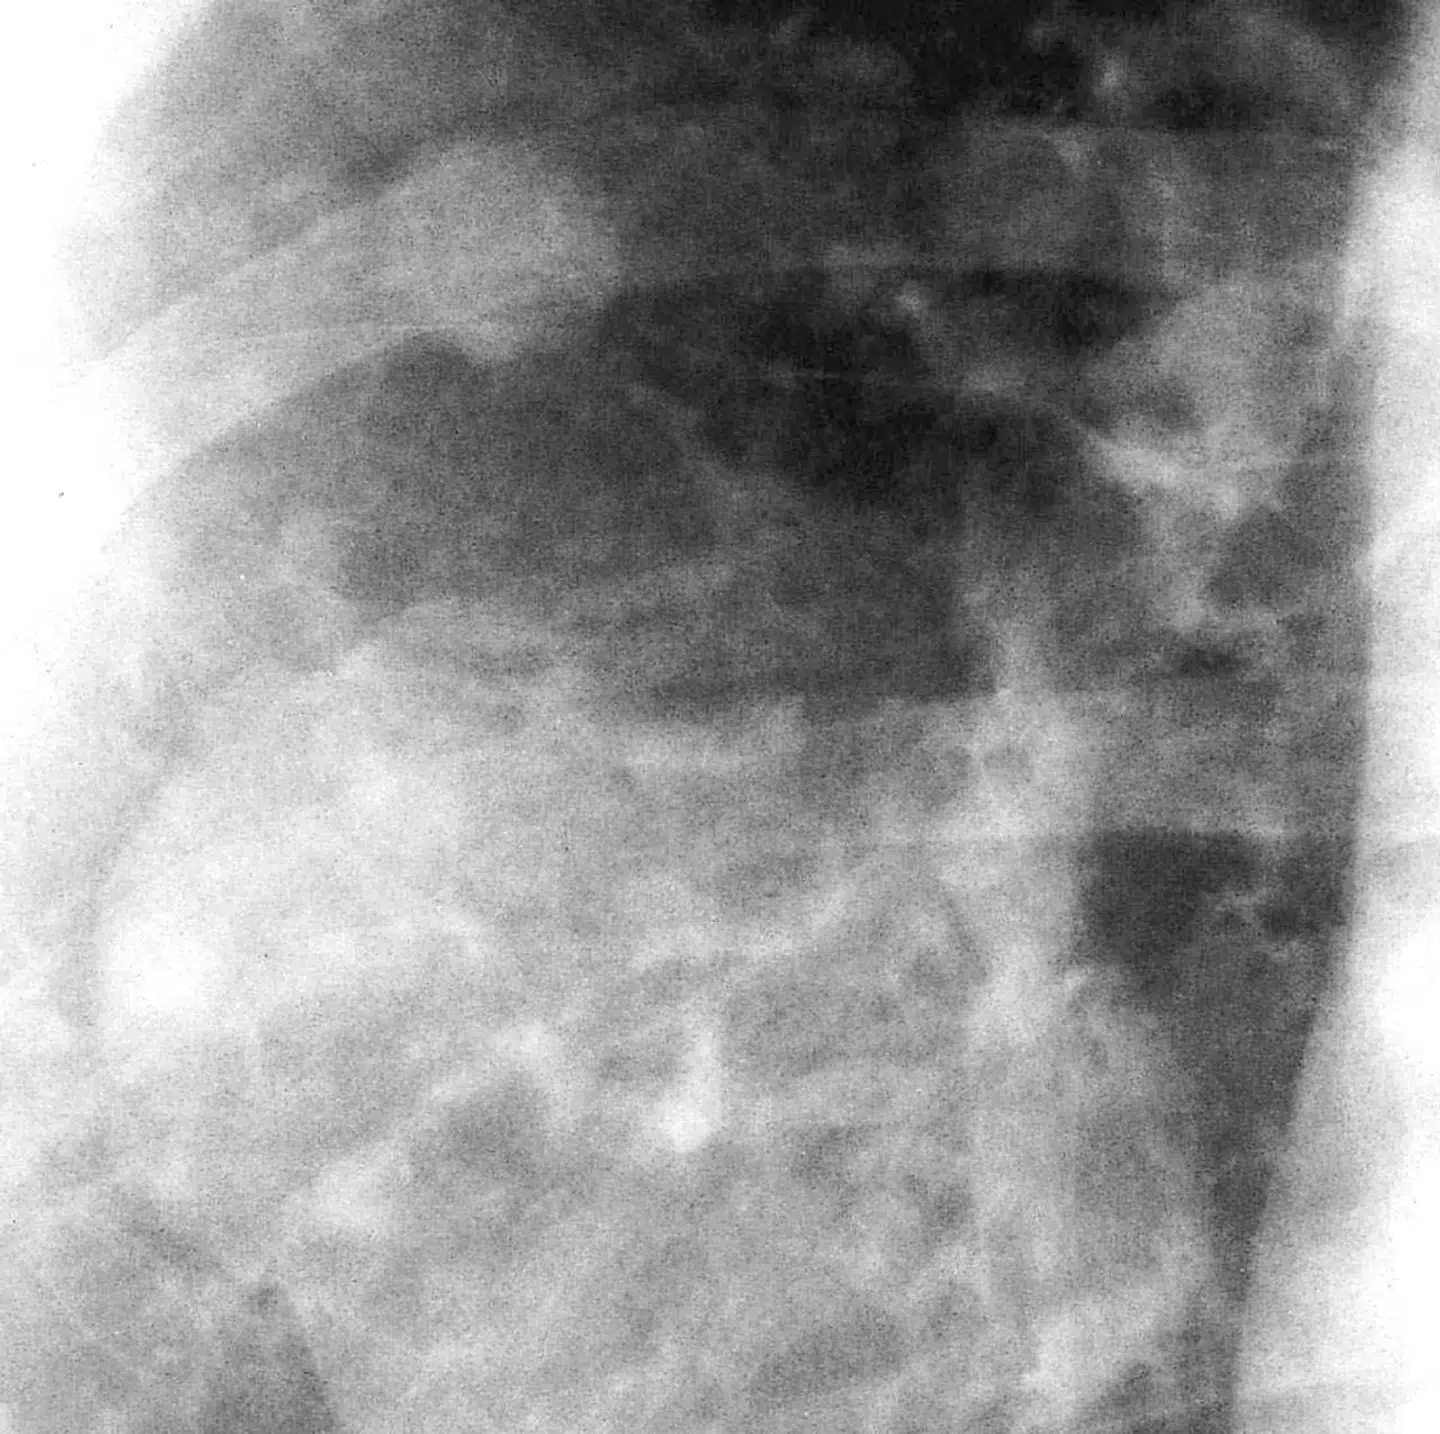

Tusindvis af patienter kommer til skade eller dør, fordi lægerne overser eller er for længe om at finde ud af, hvad de fejler. Ifølge en ny rapport er der de seneste ti år udbetalt over to milliarder kroner i erstatning for skader efter diagnosefejl. Det er dybt alvorligt, og det må der handles på, lyder det fra patienter, læger og politikere.